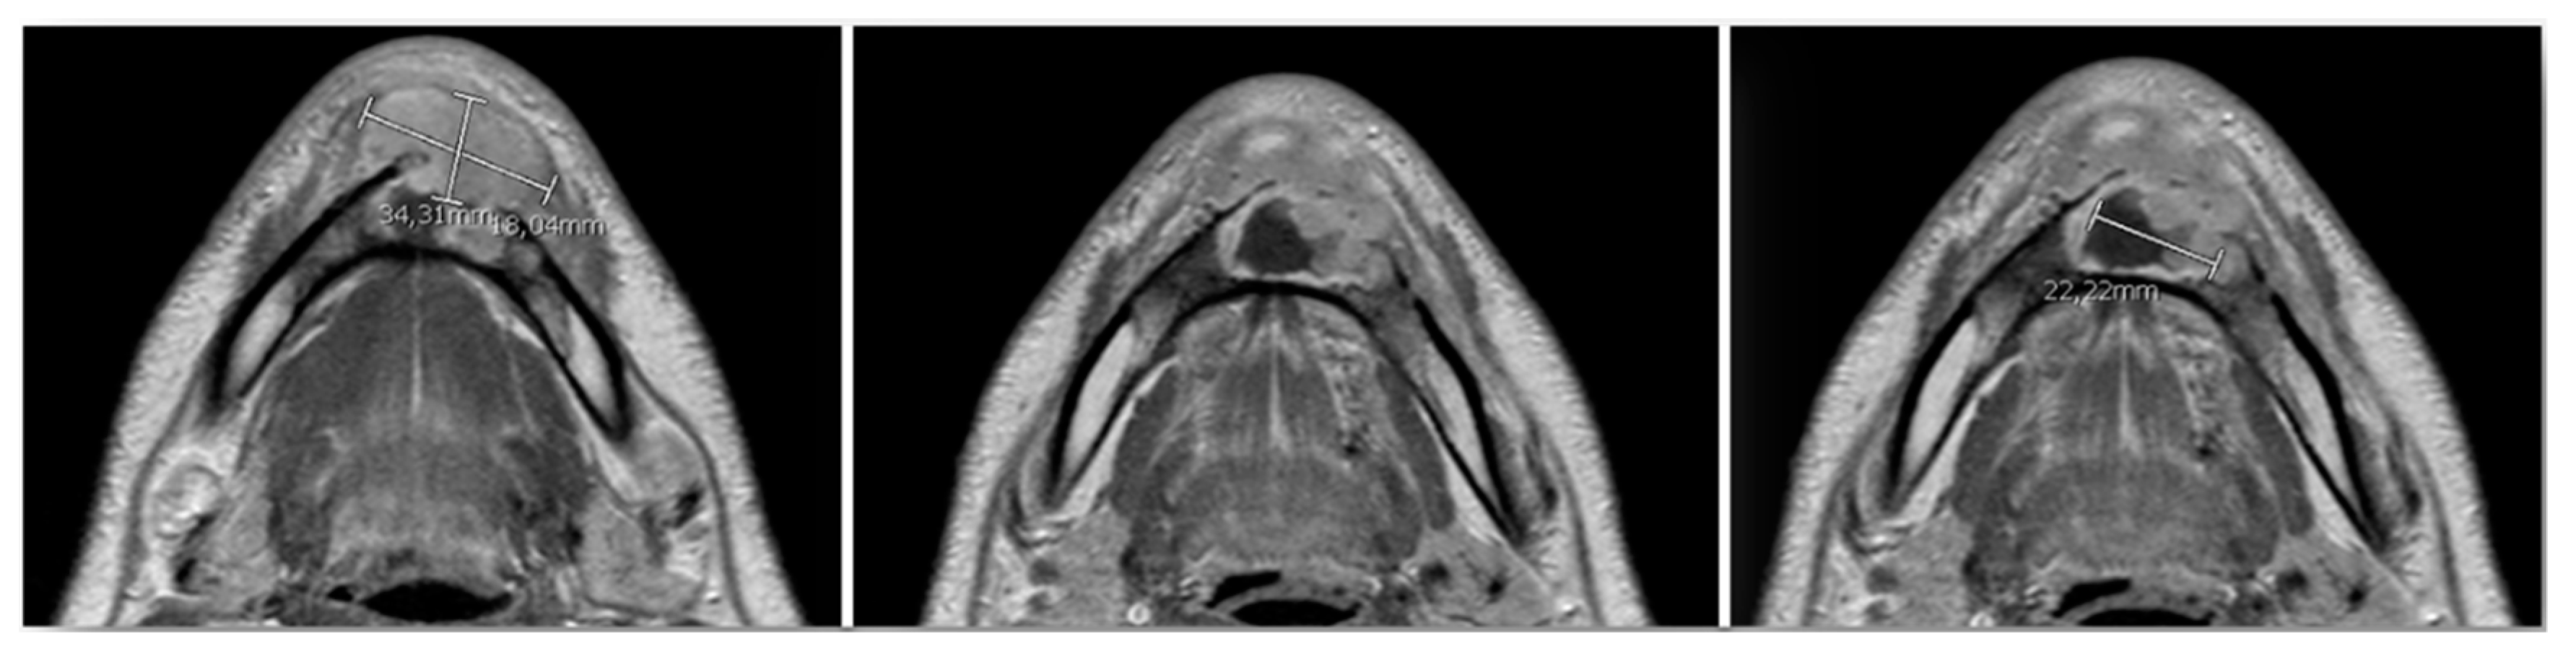

| 22 May 2017 | Admission of the patient and surgical intervention | Segmental mandibulectomy (Type C defect according to Jewer et al. [18] and Type IB according to Cordeiro [19,20] + elective bilateral lymph node (levels I-III) neck dissection + reconstruction with osteo-septo-cutaneous free fibula flap |